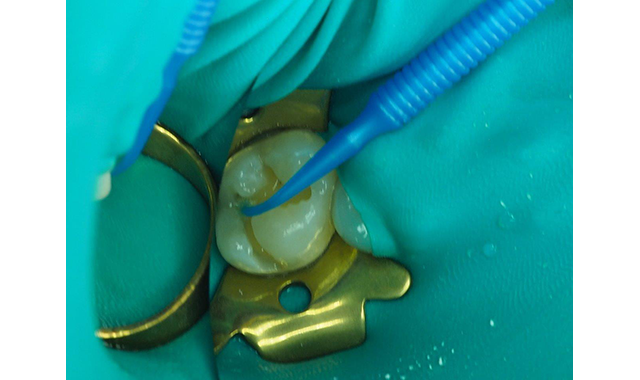

Due to the patient’s history of postoperative sensitivity, a layer of Shield Force Plus desensitizer was carefully applied only to the prepared dentin. Shield Force Plus was allowed to infiltrate the dentin for 10 plus seconds, followed by a stream of light air for 5 seconds, then strong air for five additional seconds, and finally, it was light polymerized for 10 seconds (Figs. 4,5).

Fig. 4 Shield Force Plus is dispensed into a dappen dish. This is done just prior to applying the material to prevent evaporation of solvents.

Fig. 5 The Shield Force Plus applied to the dentin for 10 seconds, slowly air-dried for 5 seconds followed by 5 seconds of strong air drying, and then light-cured for 10 seconds.